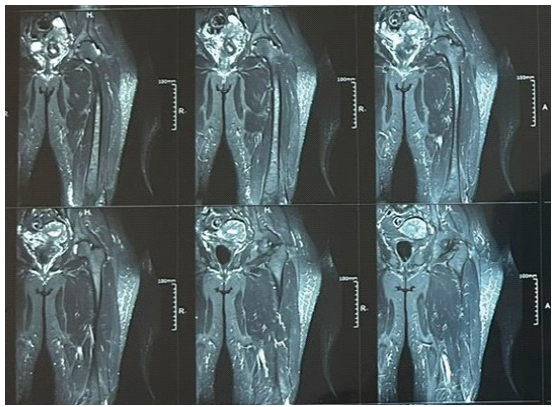

A 45-year-old female, housewife by occupation, presented to the Orthopaedic outpatient department at MMIMSR, Mullana, with a chief complaint of pain in the anteromedial aspect of the left proximal thigh for the past 1½ months. The pain was insidious in onset, non-radiating, and gradually progressive. Initially, it was relieved with rest, but later became persistent and interfered with her daily household activities, particularly while climbing stairs, squatting, and rising from a seated position. She denied any history of fall, trauma, overexertion, or vigorous physical activity before the onset of symptoms. There were no systemic comorbidities, such as diabetes, thyroid dysfunction, or chronic steroid intake. Her menstrual history was regular, and she had not yet attained menopause. She reported no history of osteoporotic fractures, bisphosphonate or corticosteroid use, or any metabolic bone disorders. There was no family history of osteoporosis, malignancy, or other skeletal diseases. Her diet was vegetarian with suboptimal calcium intake, and she had no history of tobacco or alcohol consumption. Her routine as a housewife involved moderate physical activity, including frequent squatting and kneeling. On clinical examination, she walked with an antalgic gait, favoring the left lower limb. No visible swelling, deformity, or skin discoloration was noted. Localized tenderness was elicited over the anteromedial aspect of the proximal femur, just distal to the lesser trochanter. There was no warmth or erythema. Movements of the left hip were painful, particularly flexion and internal rotation. Limb lengths were equal, and distal neurovascular status was intact. Initial anteroposterior and lateral radiographs of the pelvis and left femur showed no abnormalities—no cortical discontinuity, periosteal reaction, or signs of bone pathology. However, due to the persistence of symptoms and worsening pain on activity, a pelvic MRI was ordered. MRI revealed a hypointense linear signal in the subtrochanteric region on T1-weighted images, along with hyperintense bone marrow edema in short tau inversion recovery and T2-weighted sequences (Fig. 1 and 2). A transverse fracture line was noted along the medial cortex, without displacement—consistent with an incomplete insufficiency stress fracture. There was no associated soft tissue mass or cortical thickening.

Figure 1: Magnetic resonance imaging of the left thigh showing focal cortical and periosteal thickening along the anteromedial aspect of the upper part of the femur.

Figure 2: Magnetic resonance imaging (MRI) report of the above MRI.